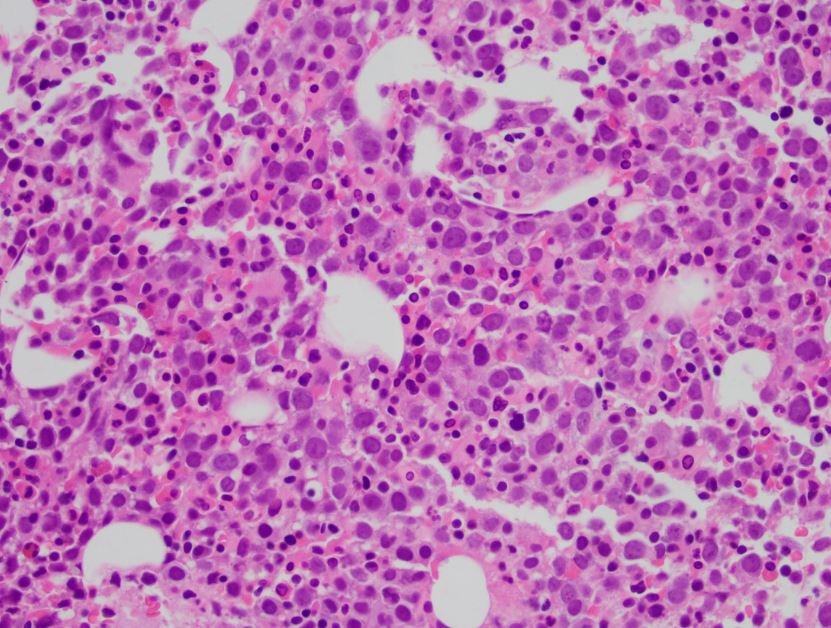

The patient is a 72 year old male with a history of HCC and plasmacytoma. The erythroid lineage is estimated at 82% with 32% pronormoblasts and 1% myeloblasts. E-cadherin and PAS stains are pictured. What is the best diagnosis?

This case meets the criteria for pure erythroid leukemia, a subtype of AML-NOS. In a pure erythroid leukemia, the erythroid lineage must comprise >80% of cells with >30% pronormoblasts. Myeloid blasts must not comprise a significant proportion of the marrow. If myeloblasts are increased to >5%, cases are classified as MDS with excess blasts. If myeloblasts are >20%, cases are classified as AML with myelodysplasia-related changes. Pure erythroid leukemia is a rare entity that is more common in patients with a preexisting MDS or as a therapy-related disease. Morphologically, there is dysplasia in the erythroid lineage cells present, often with PAS-positive cytoplasmic vacuoles, as in this case. The pronormoblasts are positive for CD71, E-cadherin, CD117, and negative for HLA-DR and CD34. Flow cytometry may not be helpful, as the erythroid lineage is lysed prior to analysis.